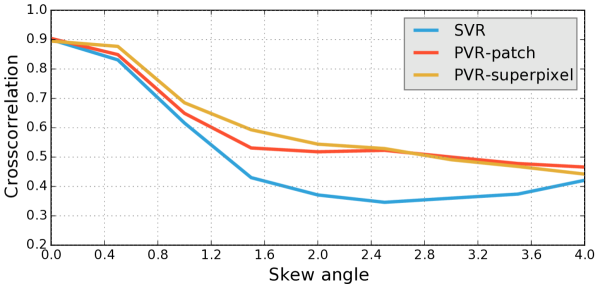

Reconstruction of Adult Brain MRI: Experiments on adult brain MR data using the Brainweb database [34] included introducing synthetic non-rigid motion artifacts as described in Sec. IV. Example slices of standard planes of original and corrupted data are depicted in Fig. 9. Comparative experimental results of SVR and PVR reconstruction methods are shown in Fig. 10 for PSNR, SSIM and CC. For all metrics, PVR shows an improved performance over SVR, particularly in presence of deformations with higher skewing angles. Further, we observe that superpixel-based PVR achieves similar performance as PVR using arbitrary square patches, while requiring a lower amount of input patches.